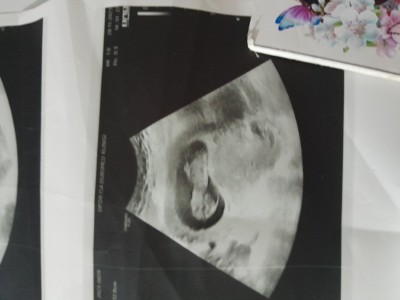

Sadece can sıkıntısı cinsiyet tahmini :)

Haydi bakalımmmmm

Erkek geçti gönlümden

İçimden erkek geçti ama kaç haftalık daha minik gibi duruyor ❤️

11+3 canım .doktor da erkek gibi ama bidakine netleşir dedi :)